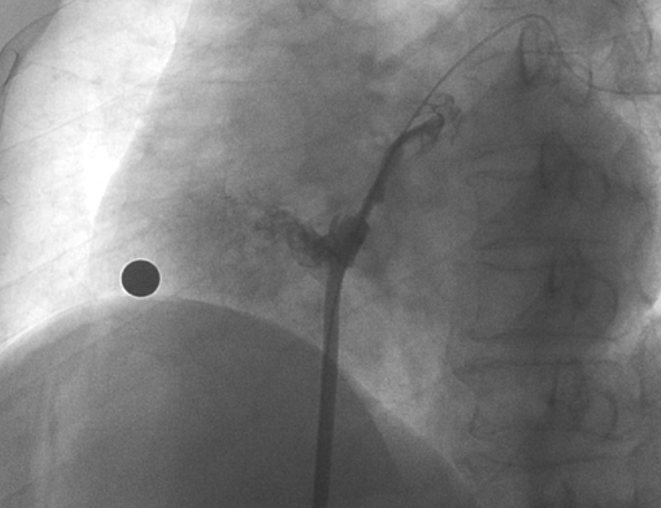

在本次植入手術(shù)中,接受介入封堵術(shù)的是一名卵圓孔未閉(長隧道型)的患者。患者60歲,男性,7年前曾診斷腦梗死,此次因新發(fā)腦梗死入院,無房顫及頸動(dòng)脈狹窄;經(jīng)胸心臟超聲和心臟聲學(xué)造影檢查提示卵圓孔未閉,Valsalva動(dòng)作后心房水平大量右向左分流。經(jīng)儲(chǔ)慧民教授團(tuán)隊(duì)評(píng)估,結(jié)合相關(guān)病史并考慮PFO及不明原因卒中,遂決定對(duì)患者開展經(jīng)皮PFO封堵術(shù)。

術(shù)中造影顯示患者為PFO且長隧道型,目前市場上已商業(yè)化的PFO封堵器難以滿足該患者解剖結(jié)構(gòu)封堵需求。迪創(chuàng)醫(yī)療自主研發(fā)的OmniSeal PFO封堵器自適應(yīng)性雙盤貼合設(shè)計(jì)能廣泛適應(yīng)不同PFO隧道長度的解剖結(jié)構(gòu)和形態(tài),其雙盤外包覆式阻流和隧道內(nèi)填充阻流相結(jié)合的雙重阻流設(shè)計(jì),可為此患者實(shí)現(xiàn)有效封堵。與此同時(shí),OmniSeal首創(chuàng)的完全可穿刺式設(shè)計(jì),也為此患者最大程度地保留了房間隔區(qū)域穿刺通道,以實(shí)現(xiàn)全兼容未來可能的左心系統(tǒng)二次介入術(shù)。術(shù)終造影和心臟超聲顯示封堵完全、效果良好。作為OmniSeal的首例臨床應(yīng)用,本次手術(shù)的順利完成和優(yōu)異效果充分體現(xiàn)了產(chǎn)品的設(shè)計(jì)創(chuàng)新優(yōu)勢。

造影顯示長隧道型PFO